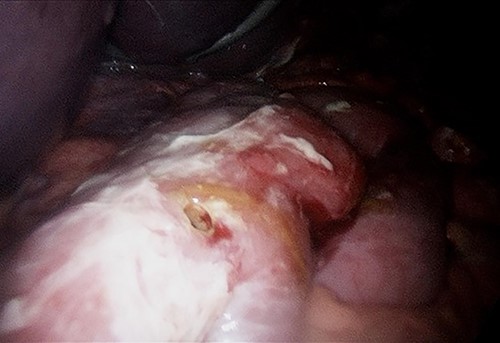

A computed tomography (CT) scan of the abdomen and pelvis showed moderate volume free gas without a clear source (Fig. 1). At diagnostic laparoscopy, there was four-quadrant purulent peritonitis and a 5-mm anterior perforation in the alimentary limb located ~15 cm from the gastrojejunostomy (Fig. 2). This was repaired laparoscopically with primary closure after excision of the ulcer edges; the histology revealed no malignancy nor Helicobacter pylori. The patient had an uneventful recovery and was discharged on post-operative day 5.